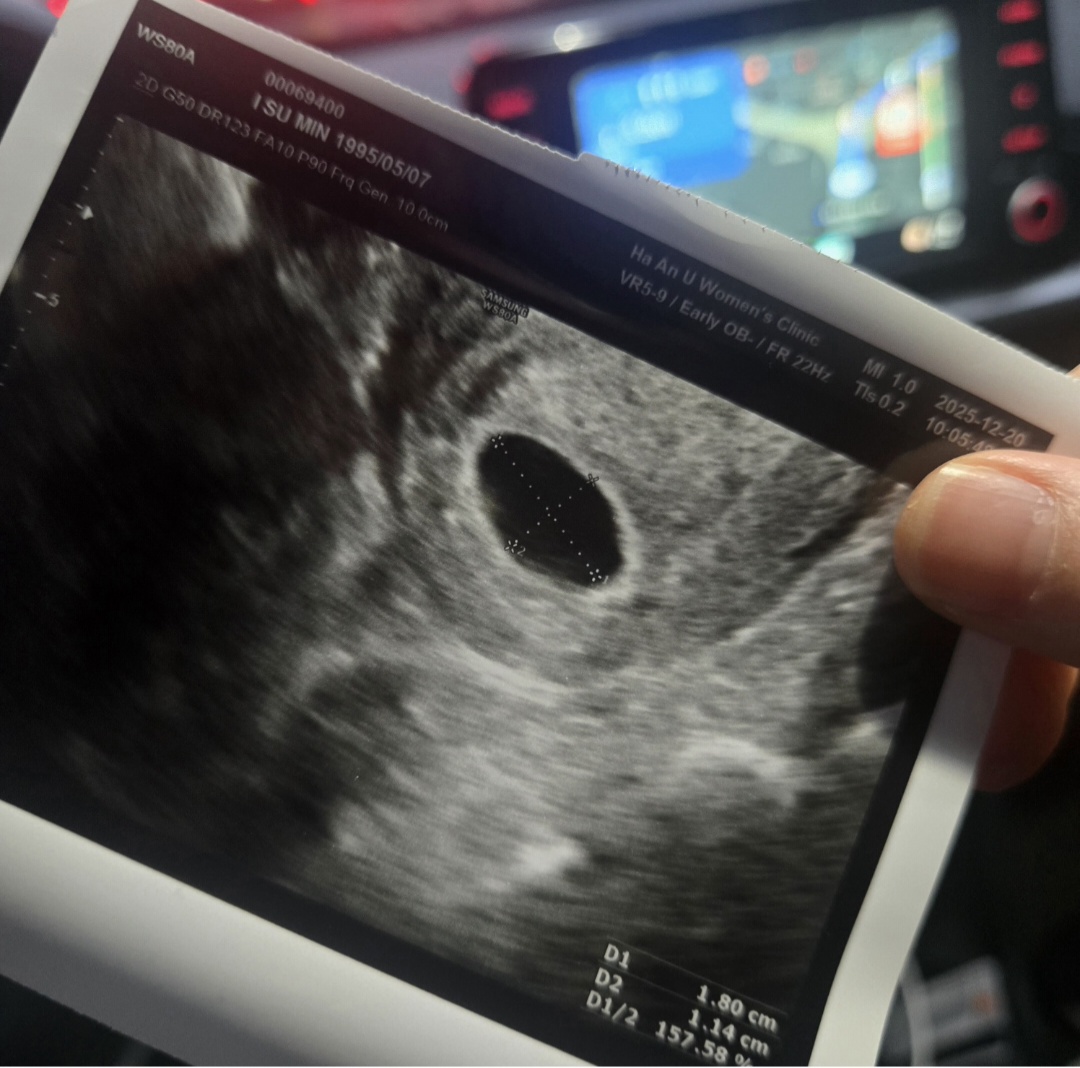

6주5일차인데아기집은참자리잘잡앗는데 난황이안보여요다음주에 수술결정날꺼같은데다른병원도가봐야할까요..